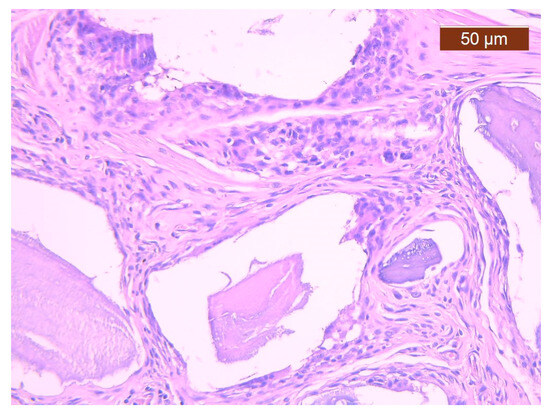

For the BS + PRF group, a similar healing trend was observed, with the incorporation of devitalized bone fragments supported by fibrous connective tissue (Figure 3). As compared to BS cases, a reduced capillary density was identified (which may represent a closer trend towards healing). In contrast, the giant cell foreign body reaction was slightly more frequent for these cases compared to those treated with BS.

Figure 3. Fibrous callus that includes bone graft fragments, an inflammatory reaction and capillaries less frequently than in the BS group. Histological snapshot from the BS + PRF study group (magnification 20×).